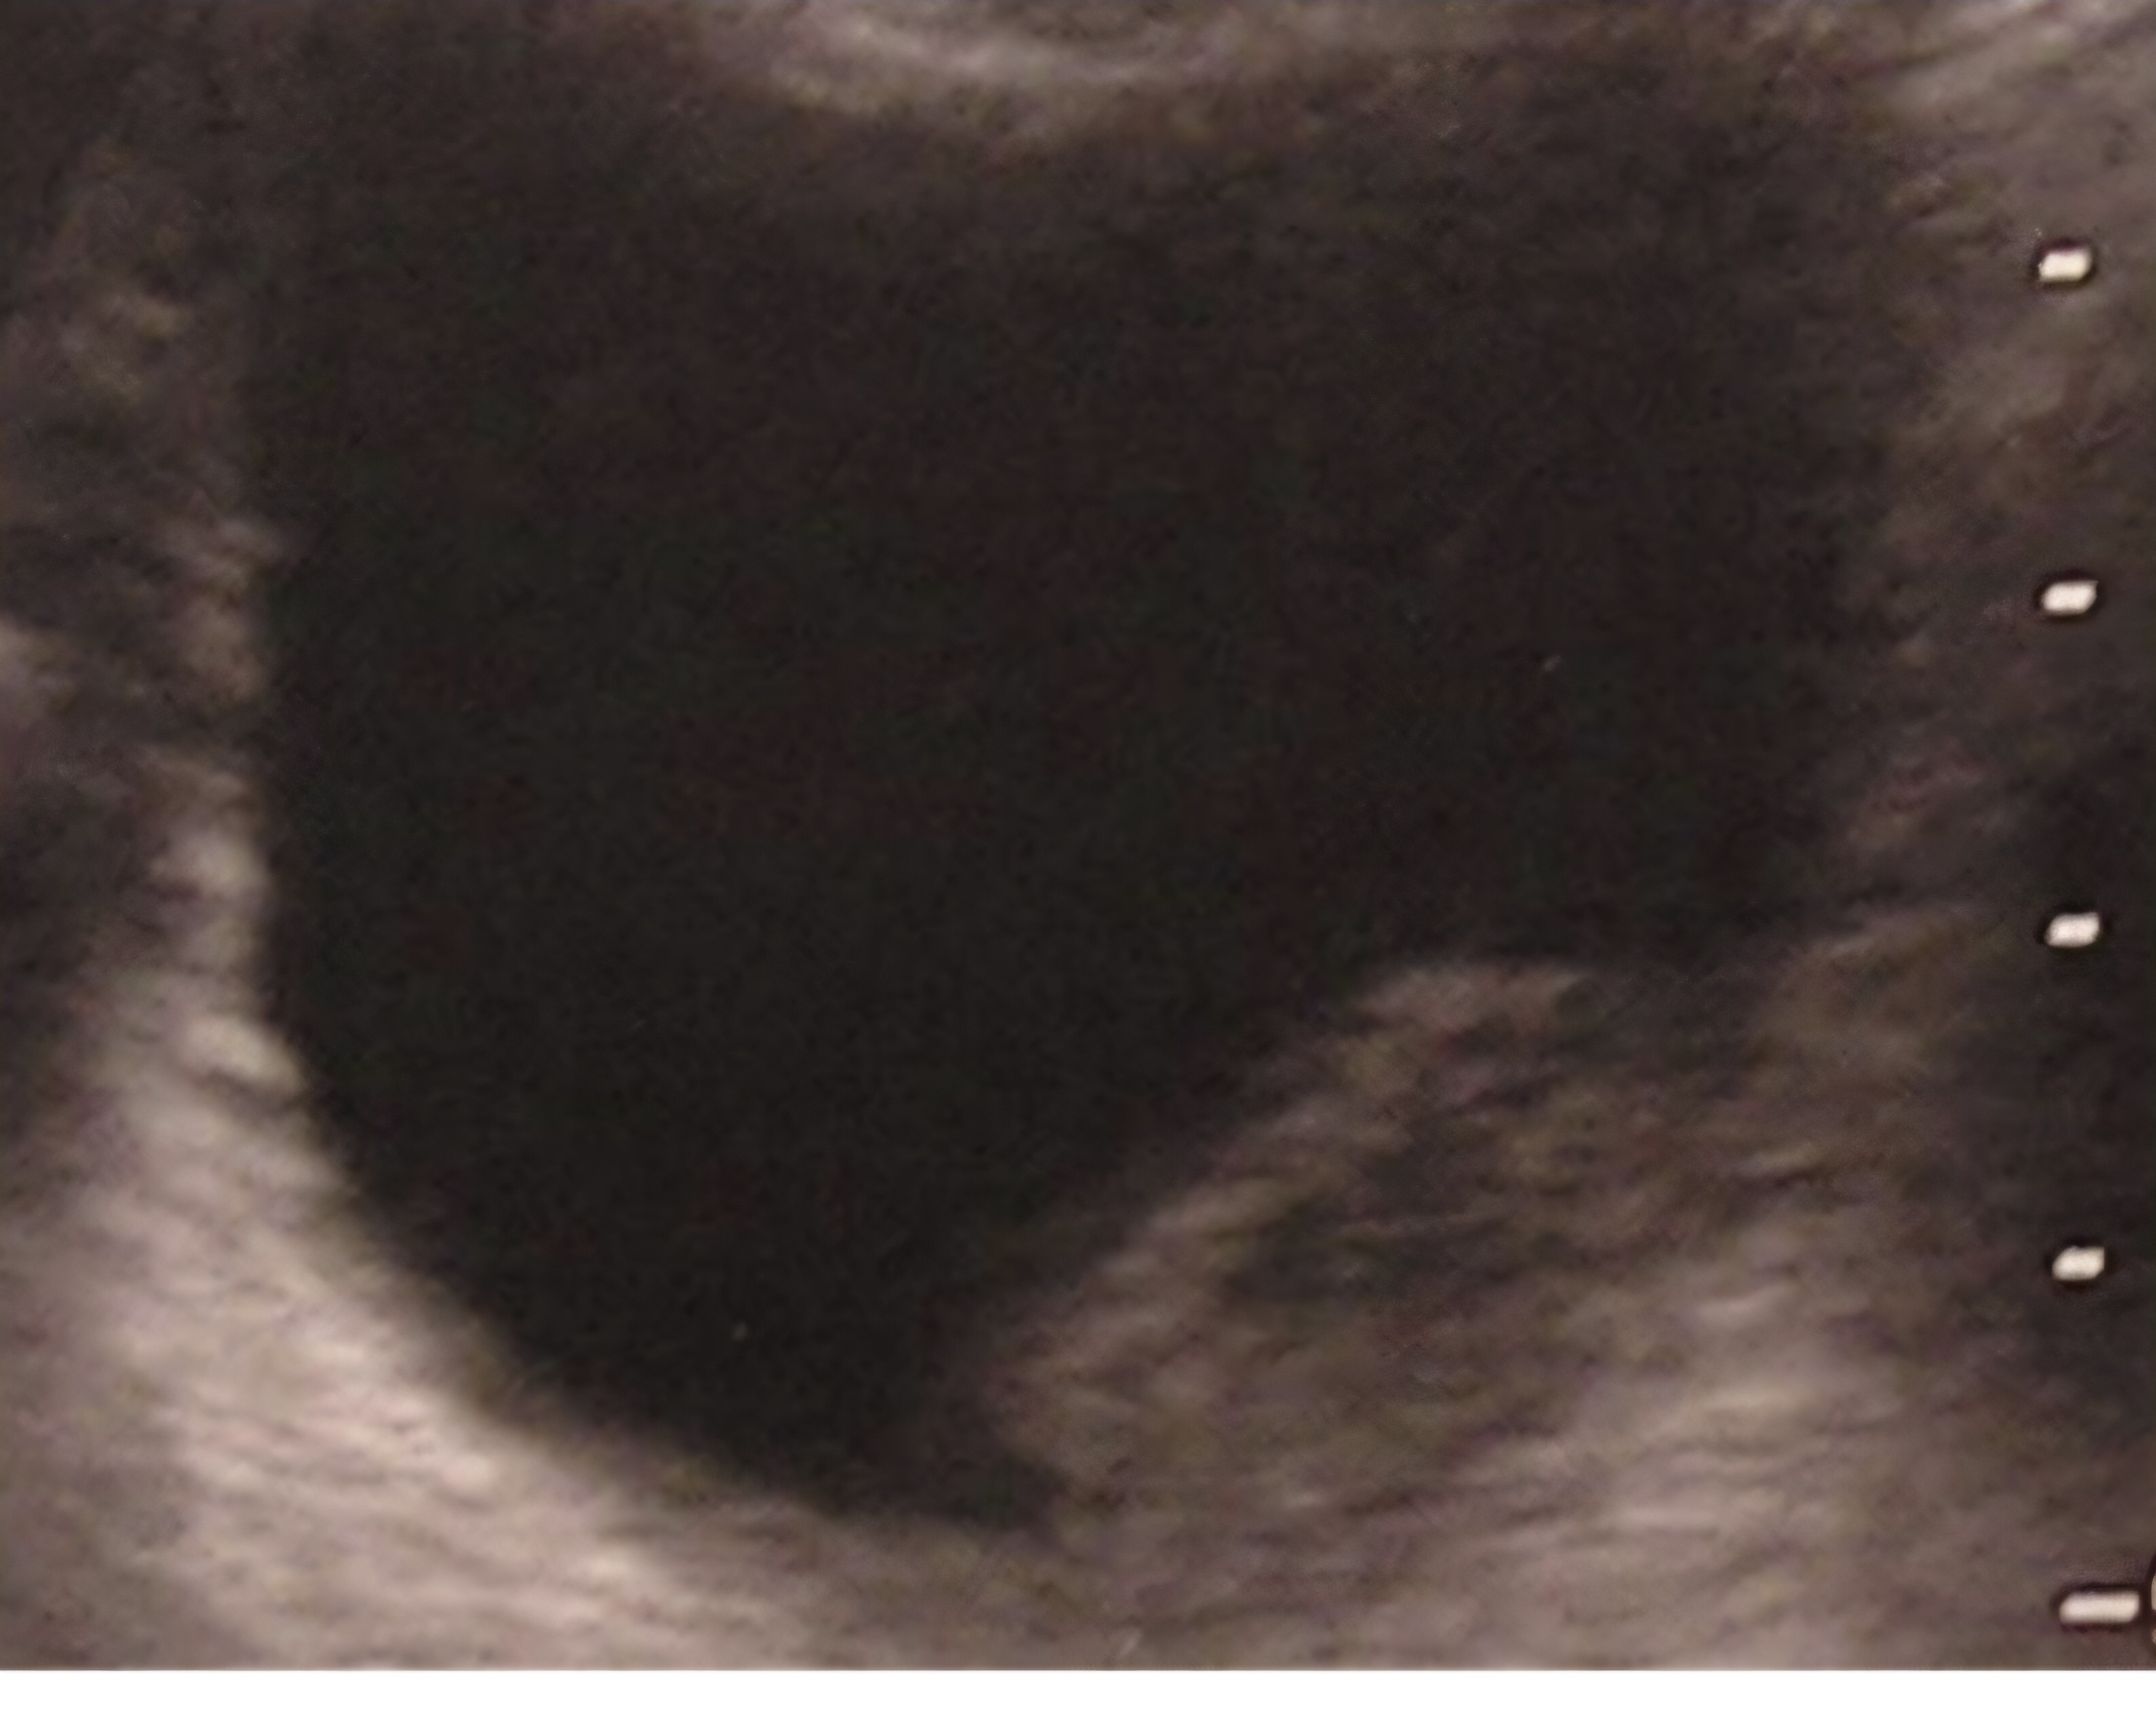

Tratamiento y planes de actuación: en sala de espera, se procede a la colocación de sonda vesical con llave de 3 pasos para lavado vesical continuo. Decidí en presencia de mi adjunto realizar una ecografía abdominal a pie de cama ante la alta sospecha de proceso neoplásico, encontrándonos como hallazgo una imagen compatible con tumor vesical y un coágulo adherido a la pared, esto nos permitió tener una impresión diagnóstica al momento y agilizar el proceso para derivación y terapéutica.

Lavado vesical efectivo y sin incidencias. Se decide interconsultar con Urólogo de guardia, quien indica derivar al paciente a Consulta de Diagnóstico Rápido.Ante la alta sospecha de tumor vesical y teniendo a nuestro alcance una herramienta diagnóstica rápida e inocua como es la ecografía, esto nos permite confirmar la sospecha diagnóstica con una alta sensibilidad (95%).